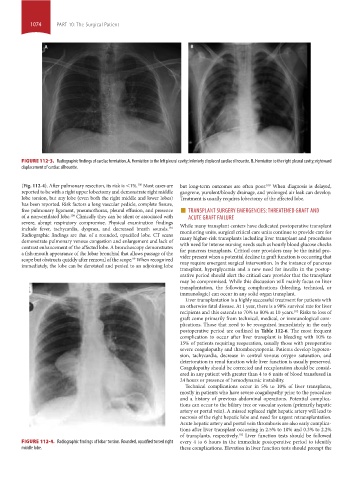

FIGURE 112-4. Radiographic findings of lobar torsion. Rounded, opacified torsed right every 4 to 6 hours in the immediate postoperative period to identify

middle lobe. these complications. Elevation in liver function tests should prompt the

Radiographic findings are that of a rounded, opacified lobe. CT scans

contrast enhancement of the affected lobe. A bronchoscopy demonstrates

a fish-mouth appearance of the lobar bronchial that allows passage of the for pancreas transplants. Critical care providers may be the initial pro-

scope but obstructs quickly after removal of the scope. When recognized

immediately, the lobe can be derotated and pexied to an adjoining lobe may require emergent surgical intervention. In the instance of pancreas